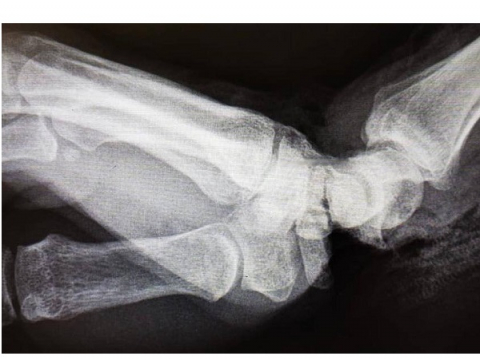

Согласно информации, пострадавшая повредила руку на производстве во Владимире. Женщина получила удар ножом для резки плёнки в область сочленения и предплечья. Когда её привезли в БСМП Владимира, кисть руки была почти оторвана и держалась лишь на небольшом лоскуте кожи.

После остановки кровотечения пациентку в экстренном порядке транспортировали в клинику ПИМУ. В отделении травматологии и ортопедии пострадавшую прооперировали. Кисть руки удалось спасти.